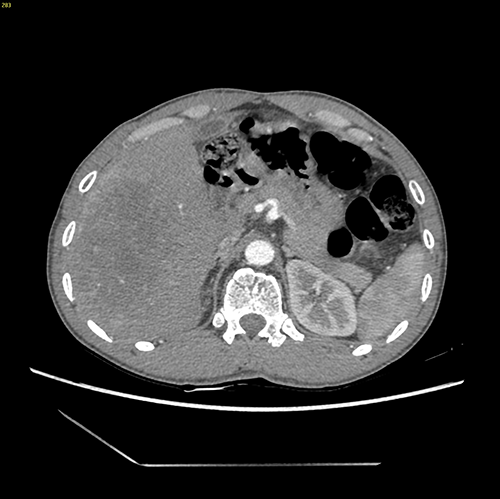

右肝癌----右肝部分切除